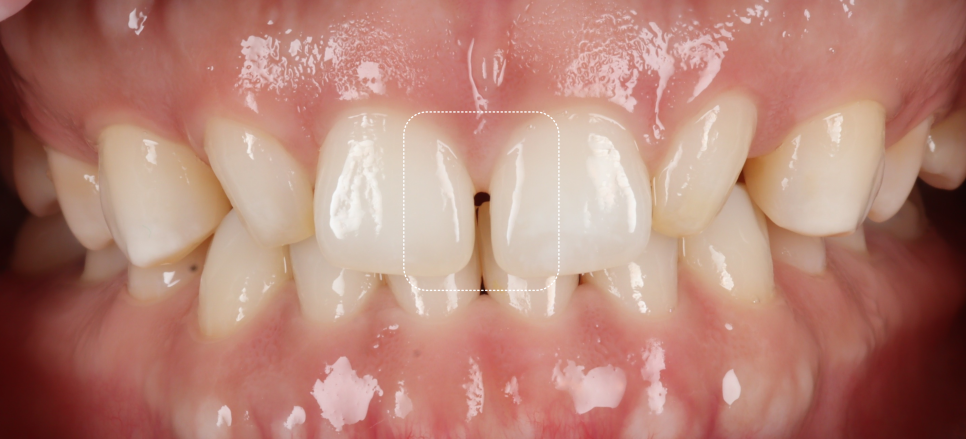

가장 먼저 눈에 띈 건, 가운데 앞니 사이가 살짝 벌어져 있었지만 정작 환자분이 처음 꺼낸 말은 이거였어요.

“이 치아가 너무 작아 보여요.”

바로 왜소치였어요. 환자분은 벌어진 것보다 왜소치가 더 거슬린다고 하셨습니다.

먼저 크기가 작은 곳부터 정상 비율로 만들 예정이에요.

문제는 왜소치의 각도가 안쪽으로 기울어져있었다는 점입니다.

그리고 왜소치 뒤편으로 공간이 있어서 이 공간까지 메우게 되면 두 번째 앞니가 매우 커질 가능성이 있었죠.

앞니 왜소치 레진 전, 후 / 촬영일 : 251203 / 251203